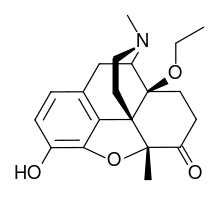

The pharmacodynamic response to an opioid depends upon the receptor to which it binds, its affinity for that receptor, and whether the opioid is an agonist or an antagonist. For example, the supraspinal analgesic properties of the opioid agonist morphine are mediated by activation of the μ1 receptor; respiratory depression and physical dependence by the μ2 receptor; and sedation and spinal analgesia by the κ receptor. Each group of opioid receptors elicits a distinct set of neurological responses, with the receptor subtypes (such as μ1 and μ2 for example) providing even more [measurably] specific responses. Unique to each opioid is its distinct binding affinity to the various classes of opioid receptors (e.g. the μ, κ, and δ opioid receptors are activated at different magnitudes according to the specific receptor binding affinities of the opioid). For example, the opiate alkaloid morphine exhibits high-affinity binding to the μ-opioid receptor, while ketazocine exhibits high affinity to ĸ receptors. It is this combinatorial mechanism that allows for such a wide class of opioids and molecular designs to exist, each with its own unique effect profile. Their individual molecular structure is also responsible for their different duration of action, whereby metabolic breakdown (such as N-dealkylation) is responsible for opioid metabolism.

Several semi-synthetic opioids were developed in Germany in the 1910s. The first, oxymorphone, was synthesized from thebaine, an opioid alkaloid in opium poppies, in 1914.[228] Next, Martin Freund and Edmund Speyer developed oxycodone, also from thebaine, at the University of Frankfurt in 1916.[229] In 1920, hydrocodone was prepared by Carl Mannich and Helene Löwenheim, deriving it from codeine. In 1924, hydromorphone was synthesized by adding hydrogen to morphine. Etorphine was synthesized in 1960, from the oripavine in opium poppy straw. Buprenorphine was discovered in 1972.[228]